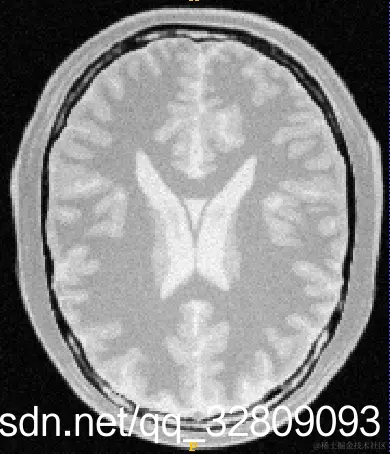

输入三维图像(BrainProtonDensity3Slices.mha):

切片1                                     切片2                                        切片3